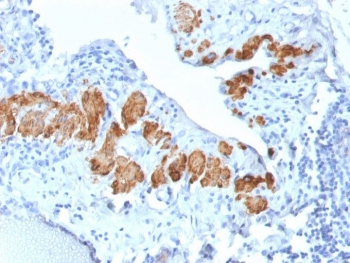

IHC: Formalin-fixed, paraffin-embedded human breast carcinoma stained with SMMHC antibody (MYH11/923).